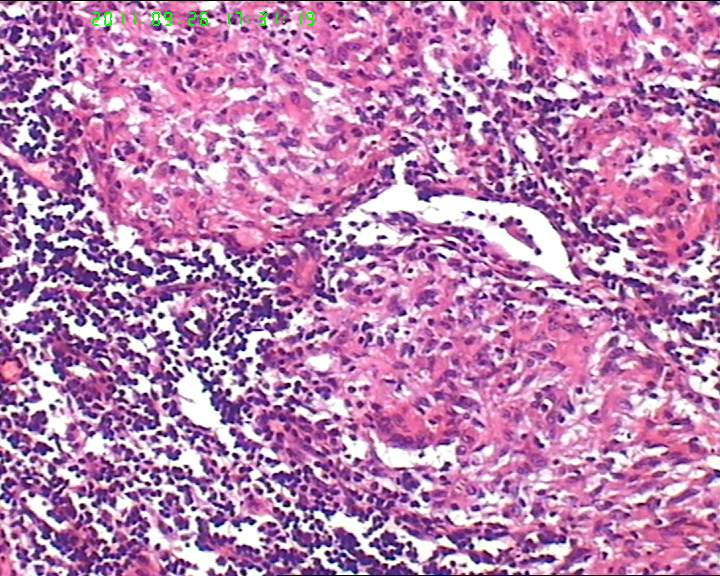

灰白不整形肿物一个,大小3.5*2.5*2cm,包膜完整。

21岁女性左侧颌下淋巴结,该诊断什么?图4

慢性肉芽肿性炎症,形态学倾向结节病,但是作为病理工作者对于这样的病例,再结合咋们国情,还是建议临床除外增殖性结核后再考虑结节病。

肉芽肿性炎症,倾向结节病。

最好做做抗酸染色、网状纤维染色和PAS后看看再定。